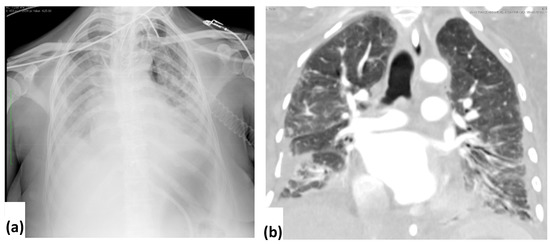

Alert Germ Infections: Chest X-ray and CT Findings in Hospitalized Patients Affected by Multidrug-Resistant Acinetobacter baumannii Pneumonia

3.2. CXR Findings and Disease Distribution

3.3. CT Findings and Disease Distribution